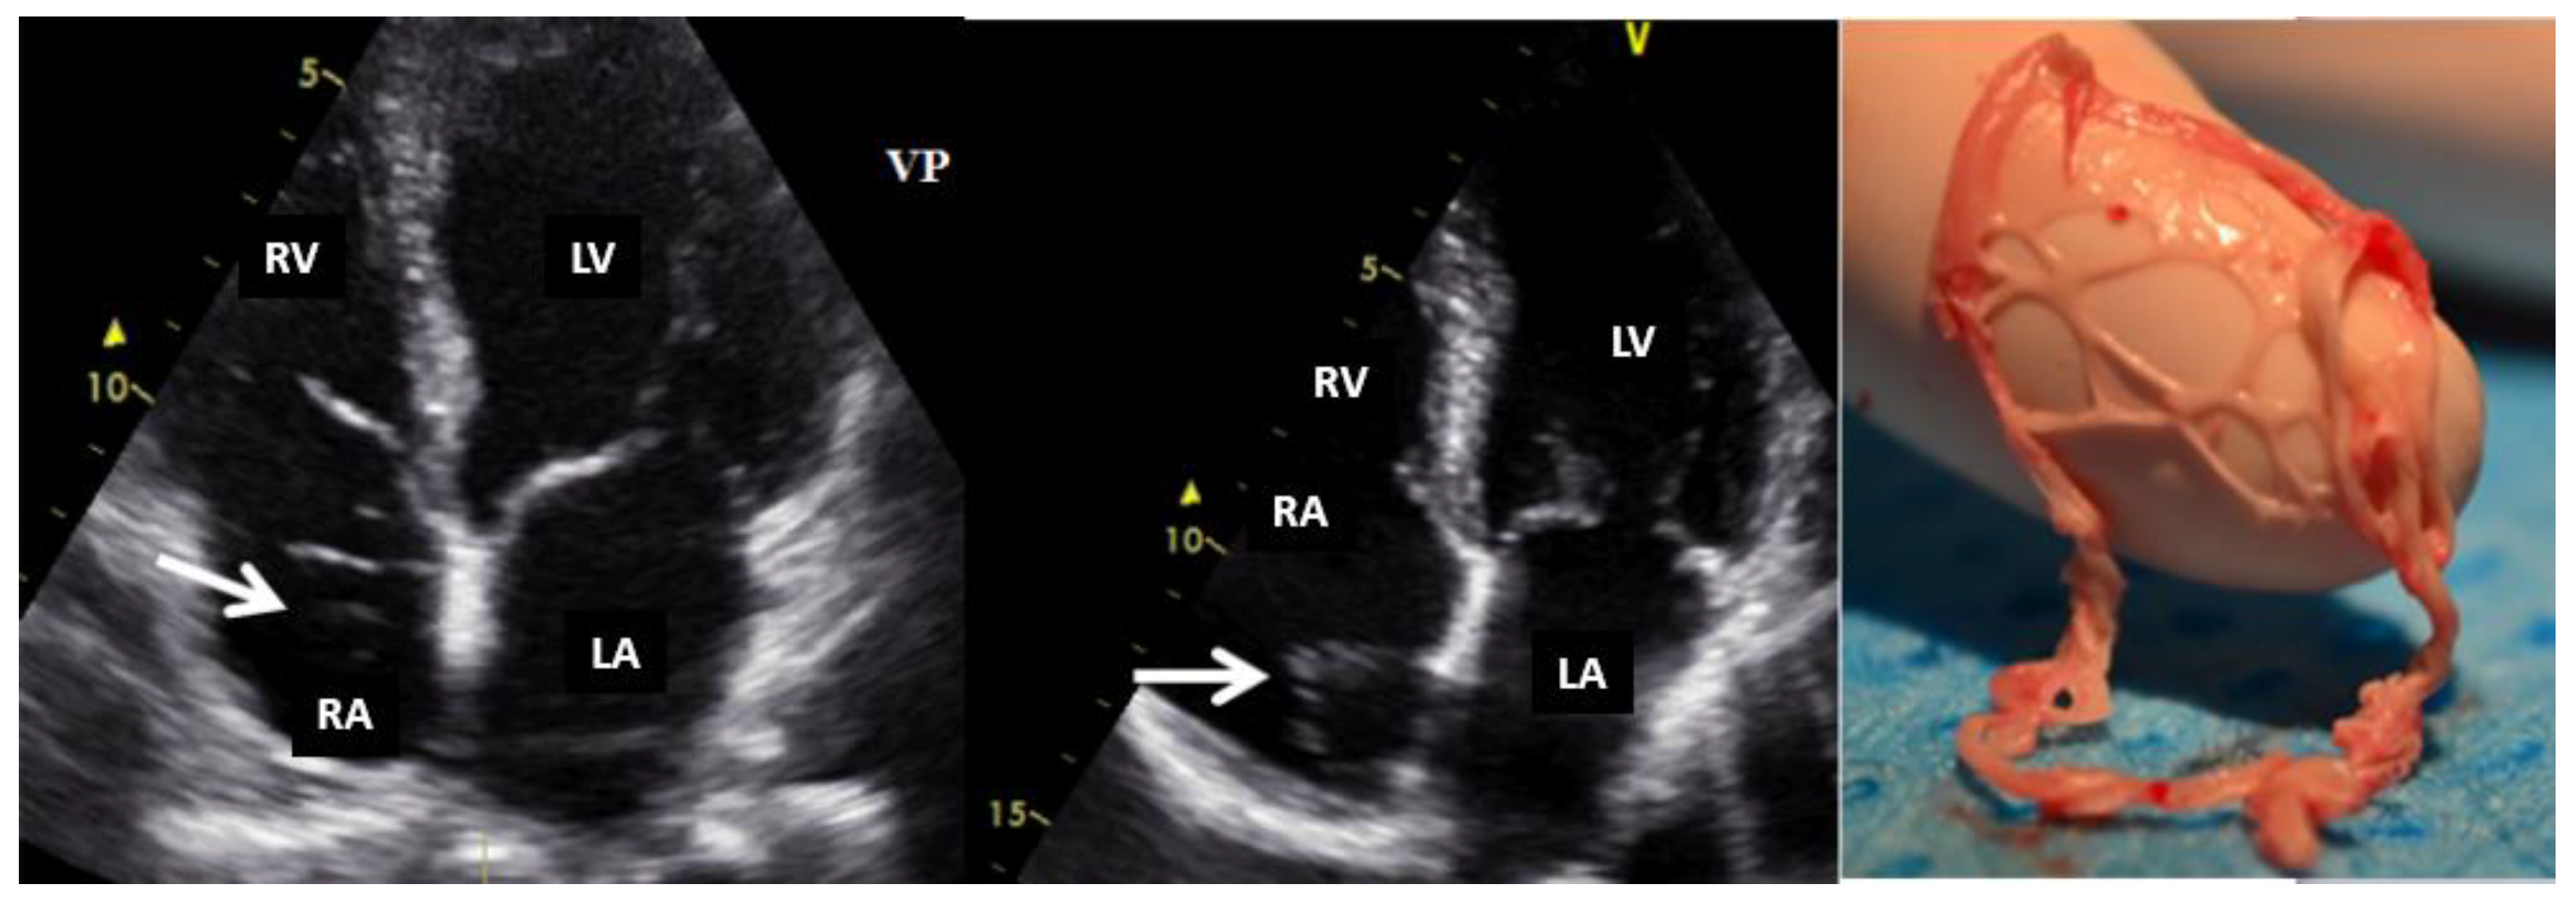

Figure 5. Bi-dimensional transesophageal echocardiography (short axis view at the level of great vessels) showing a mass on the port-a-cath in a patient with neoplasia and chemotherapy. It was an incidental finding. This mass disappeared after anticoagulation treatment because it was a thrombus. AO, aorta; IVS, interventricular septum; LA, left atrium; LV, left ventricle; RV, right ventricle.

The diagnostic approach for right heart tumors is primarily based on differentiating them from other right heart masses such as thrombi (Figure 5) or vegetation (Figure 6). For example, in a patient known with neoplasia and port-a-cath (whether undergoing chemotherapy or not), a right heart masse discovered fortuity on TTE or TEE suggests, in a first step, a thrombus on the port-a-cath (Figure 5). It was less likely to be a benign tumor, especially considering these patients underwent repeated TTE evaluations. The initiation of anticoagulant treatment can determine the disappearing of this mass. However, a differential diagnosis is mandatory, involving considerations of marantic endocarditis or metastases.